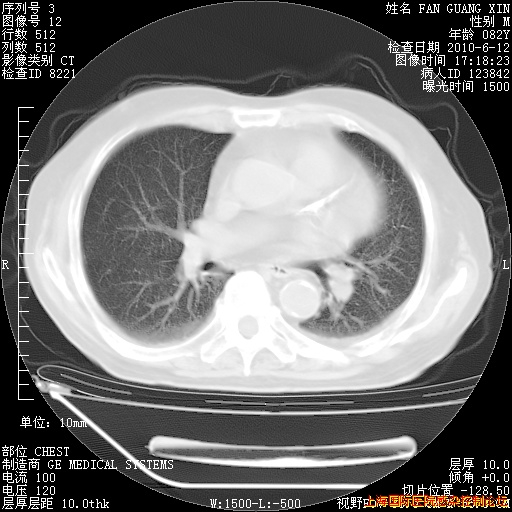

今天复查CT

今天CT

整整相隔30天的肺部CT好像有所好转啊。甲强龙减量第3天,需要观察体温。

海管,自昨日你和我通完话后,不知您岳父消化道症状有无缓解?体温怎样?阅读7.12日胸部ct,个人认为目前激素治疗是有效的,甲强龙减量是适宜的。因在抗痨治疗,需密切观察肝功、肾功能和血常规。不过,老年、长期住院和大量使用激素,很担心菌群失调发生